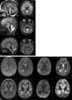

PEHO syndrome

PEHO syndrome (Progressive encephalopathy with Edema, Hypsarrhythmia and Optic atrophy) is an autosomal recessive and dominate, progressive neurodegenerative disorder that starts in the first few weeks or months of life. Early symptoms include infantile spasms, hyparrhythmia, and seizures, and optic atrophy. [Source: Wikipedia ]